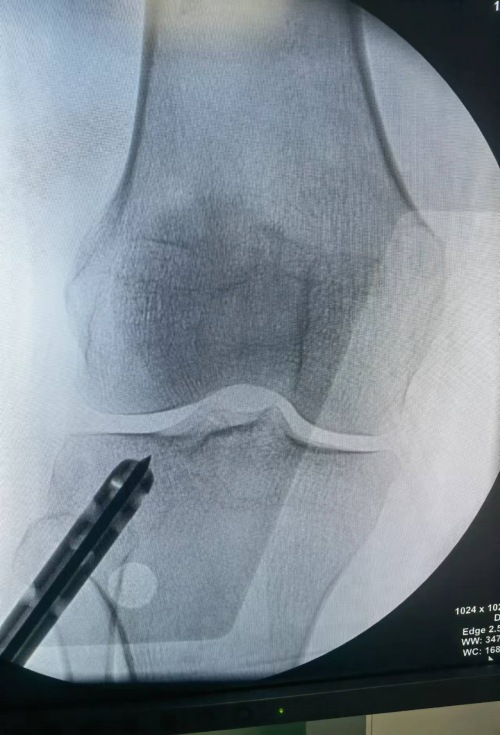

镜下观察塌陷骨折面

骨科二病区严伟主任医疗团队对该病例开展充分讨论,最后决定采用经关节镜辅助下外侧平台开孔经隧道推顶复位塌陷关节面并经皮空心螺钉内固定微创治疗。手术由严伟主任、潘守峰副主任医师主刀,在麻醉一科、手术一科的全力配合下,手术顺利完成,目前患者恢复良好,无并发症出现,术后第二天即可功能锻炼,患者表示非常满意。

顶复方法

复位后镜下观